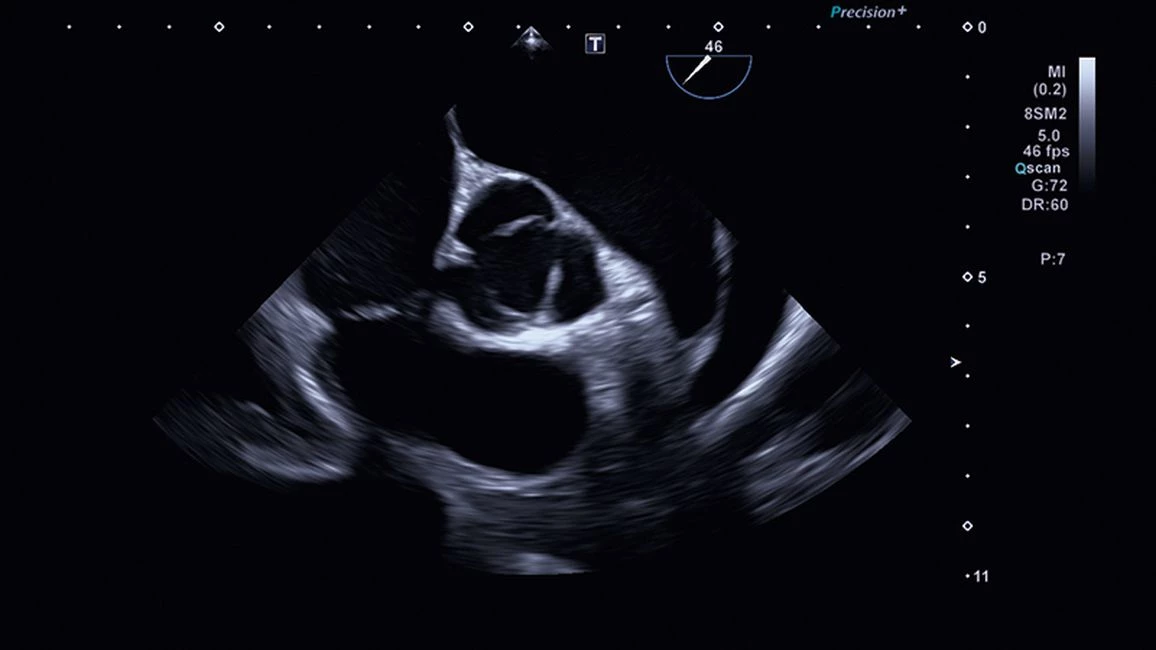

УЗИ аппарат Canon Aplio i900 — универсальный сканер премиального класса. Оснащенная обновленным пакетом 4D-функций, система считается лучшей в своем классе для исследования сердца и его визуализации. Технология максимально тщательной обработки изображения позволяет врачам ставить точные диагнозы, основываясь на контрастных и высокодетализированных снимках.

- Четырехмерная визуализация сердца в повседневной клинической практике - лучшая в своем классе

- Кардиология,

- 3D/4D сердца: ✔